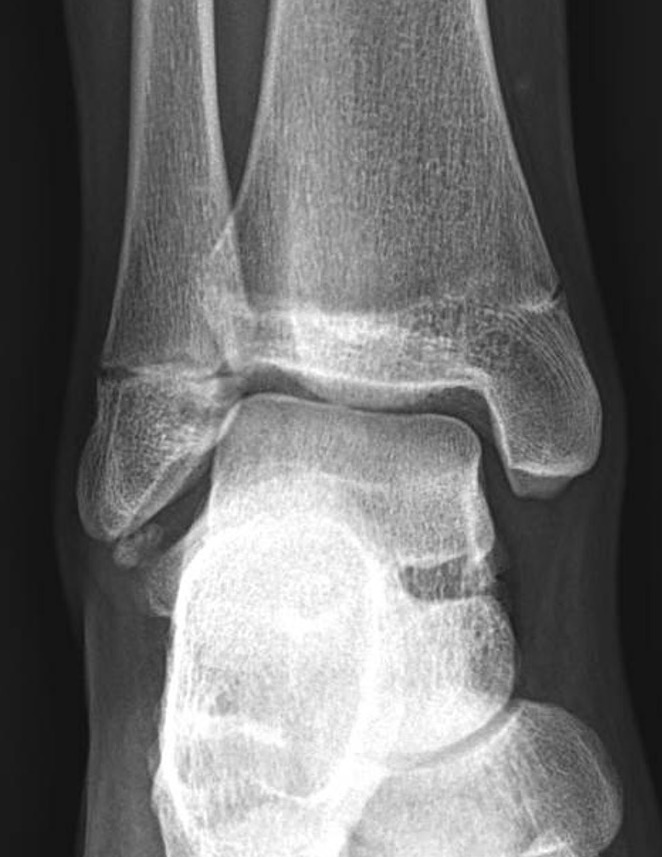

Stress Xrays

| Anterior drawer | Talar tilt |

|---|---|

| Assess ATLF | CFL test / subtalar instability |

|

10° plantarflexion neutral rotation Draw talus anterior to tibia |

10-20° plantarflexion Ankle inversion |

| > 3mm difference to other ankle | > 20o difference to other ankle |